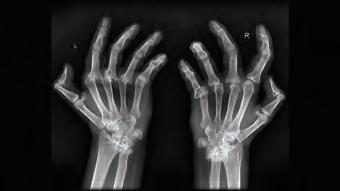

олезнь: артрит суставов Какие органы поражает: суставы, связки и кости Причины: инфекции, нарушение обмена веществ, повышенная кровоточивость из-за кровоизлияний в сустав, аутоиммунное воспаление Симптомы: боль, припухлость, покраснение кожи над пораженным суставом, ограничение подвижности, повышение температуры тела, усталость и/или слабость, нарушение аппетита Осложнения: повреждение и деформация суставов, туннельный синдром, повреждение спинного мозга Врач: терапевт, ревматолог Лечение: медикаментозное, местное, физиотерапия, массаж, гимнастика, артродез, в некоторых случаях - хирургическая замена сустава Профилактика: снижение веса, занятия спортом

– это собирательное

распространены такие виды патологии: ревматоидный, подагрический, септический, реактивный и идиопатический. Артрит и артроз – взаимосвязанные явления, но не одно и то же. Артрит – воспаление сустава, артроз –разрушение, износ сустава. Эти явления почти всегда сопровождают друг друга, но знак равенства между ними ставить нельзя.

СТАДИИ ЗАБОЛЕВАНИЯ

При артритах хронического течения фазы обострения обычно сменяются ремиссиями. Начало заболевания называется дебютом и характеризуется формированием болевого синдрома

и появлением скованности в пораженном сочленении.

Выделяют 4 стадии артрита:

• 1 стадия. На этой стадии происходит инфицирование организма, симптоматика отсутствует. Может присутствовать скованность движений, болезненные ощущения при интенсивной нагрузке на сустав.

• 2 стадия. Начинаются патологические процессы, суставные ткани истончаются, что провоцирует воспаление. На этом этапе идет возникновение эрозийных образований на кости, развивается припухлость

и поднимается температура, кожные покровы краснеют, движение суставов сопровождается хрустом.

• 3 стадия. Ограничивается подвижность, идет постоянное напряжение мышечных тканей. Развивается деформация суставной ткани. Часто людям с 3 степенью артрита присваивают инвалидность.

• 4 стадия. Изменения приобретают необратимый характер, сустав не может двигаться. Костные головки суставов сращиваются между собой. Без лечения артрит может проте-

кать агрессивно и приводит к разрушению сустава. Своевременное лечение помогает удерживать болезнь

• Пункция сустава для анализа синовиальной жидкости (при септическом артрите, гемофилии, подагре) Из инструментальных методов исследования обычно используется рентгенография суставов или компьютерная томография. С их помощью можно оценить степень сужения суставной щели и состояние